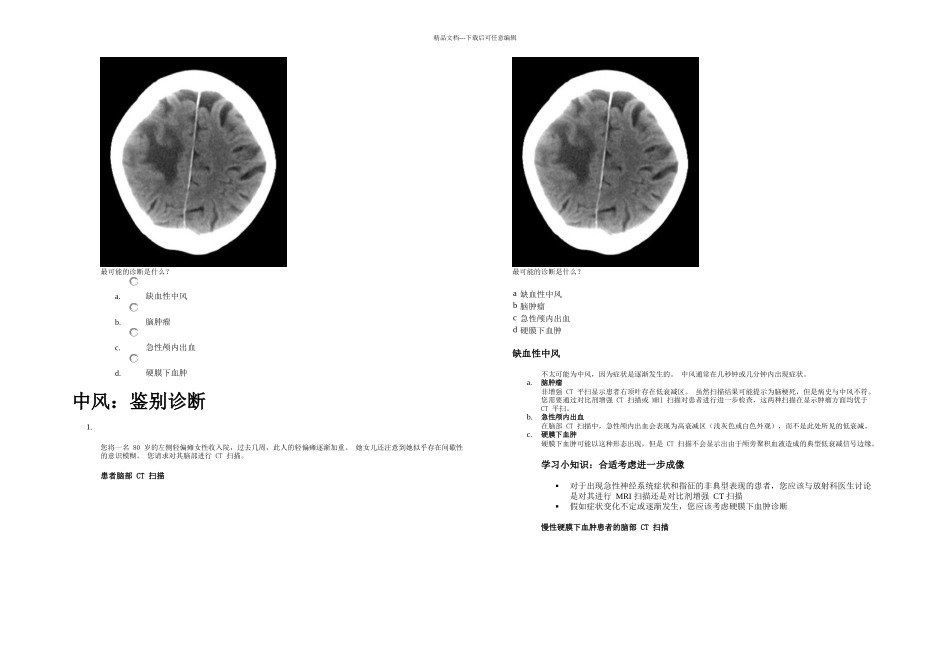

精品文档---下载后可任意编辑学习成果完成本单元后,您应该:知道中风的临床和放射学特征懂得中风的常见鉴别诊断能够辨识中风的鉴别诊断的临床和放射学特征知道怎样治疗出现急性神经系统症状的患者。"中风是一种常见内科问题。 您需要立即开展治疗以将患者长期残残或死亡的风险降至最低。 存在其它可能表现出与中风相似症状和体征的疾病。 医生能够辨识这些疾病很重要,因为它们的治疗和预后与中风不同。"临床经验中风患者需要尽快进行脑部成像,以便在溶栓治疗前排除出血可能在计算机断层 (CT) 扫描中,大脑中动脉中的血栓可能被误认为蛛网膜下腔出血假如患者出现急性神经系统症状,必须检查患者的血糖多发性硬化应始终由专科医生诊断1.您在急诊科接诊一名 33 岁的女性,最近几天她出现逐渐加重的右侧乏力和唤词困难。 四年前她出现过眩晕发作,但是无其它既往病史,且从不吸烟。 最近一次血液检查显示,她的总胆固醇水平为 4.0 mmol/l。您应该做什么?a.开始用阿司匹林和他汀类药物治疗中风b.将患者转诊给神经科医生进行明确诊断c.将患者转诊给神经外科病房a.开始用阿司匹林和他汀类药物治疗中风此例患者不太可能患有中风,因为症状是逐渐发生的,并且她不具有心血管风险因素。 中风症状通常在几秒或几分钟内迅速出现,而多发性硬化或脑肿瘤症状倾向于在数天或数周内逐渐出现。 不需要开始中风二级预防。b.将患者转诊给神经科医生进行明确诊断患者症状的时间过程提示为多发性硬化诊断。 您应该将患者转诊给神经科医生,由他们确定或推翻该诊断。 多发性硬化诊断的基础为发现两个或多个在空间和时间上独立的特征性神经系统事件。 国家指南指出,仅专家可以进行多发性硬化诊断。1下图显示了患者的脑部 MRI T2 加权扫描图像。 对患者脑部进行的 T2 加权 MRI 扫描图像显示左顶叶存在白质高信号病变。 白质高信号病变存在几个原因,包括多发性硬化,但是它们还可见于无症状者。c.将患者转诊给神经外科病房怀疑此患者患有多发性硬化。 神经外科医生不能提供给她任何有用的治疗。学习小知识:多发性硬化 1对于年龄小于 40 岁且出现局灶性神经系统症状的患者,您应该考虑多发性硬化 2根据国家指南,仅专科医生可以进行多发性硬化诊断考虑对可能患有多发性硬化的患者进行成像: MRI 是最敏感的成像方法在中枢神经系统的不同部位找到在不同时间点发生病变可支持诊断T2 加权 MRI 通常显示白...